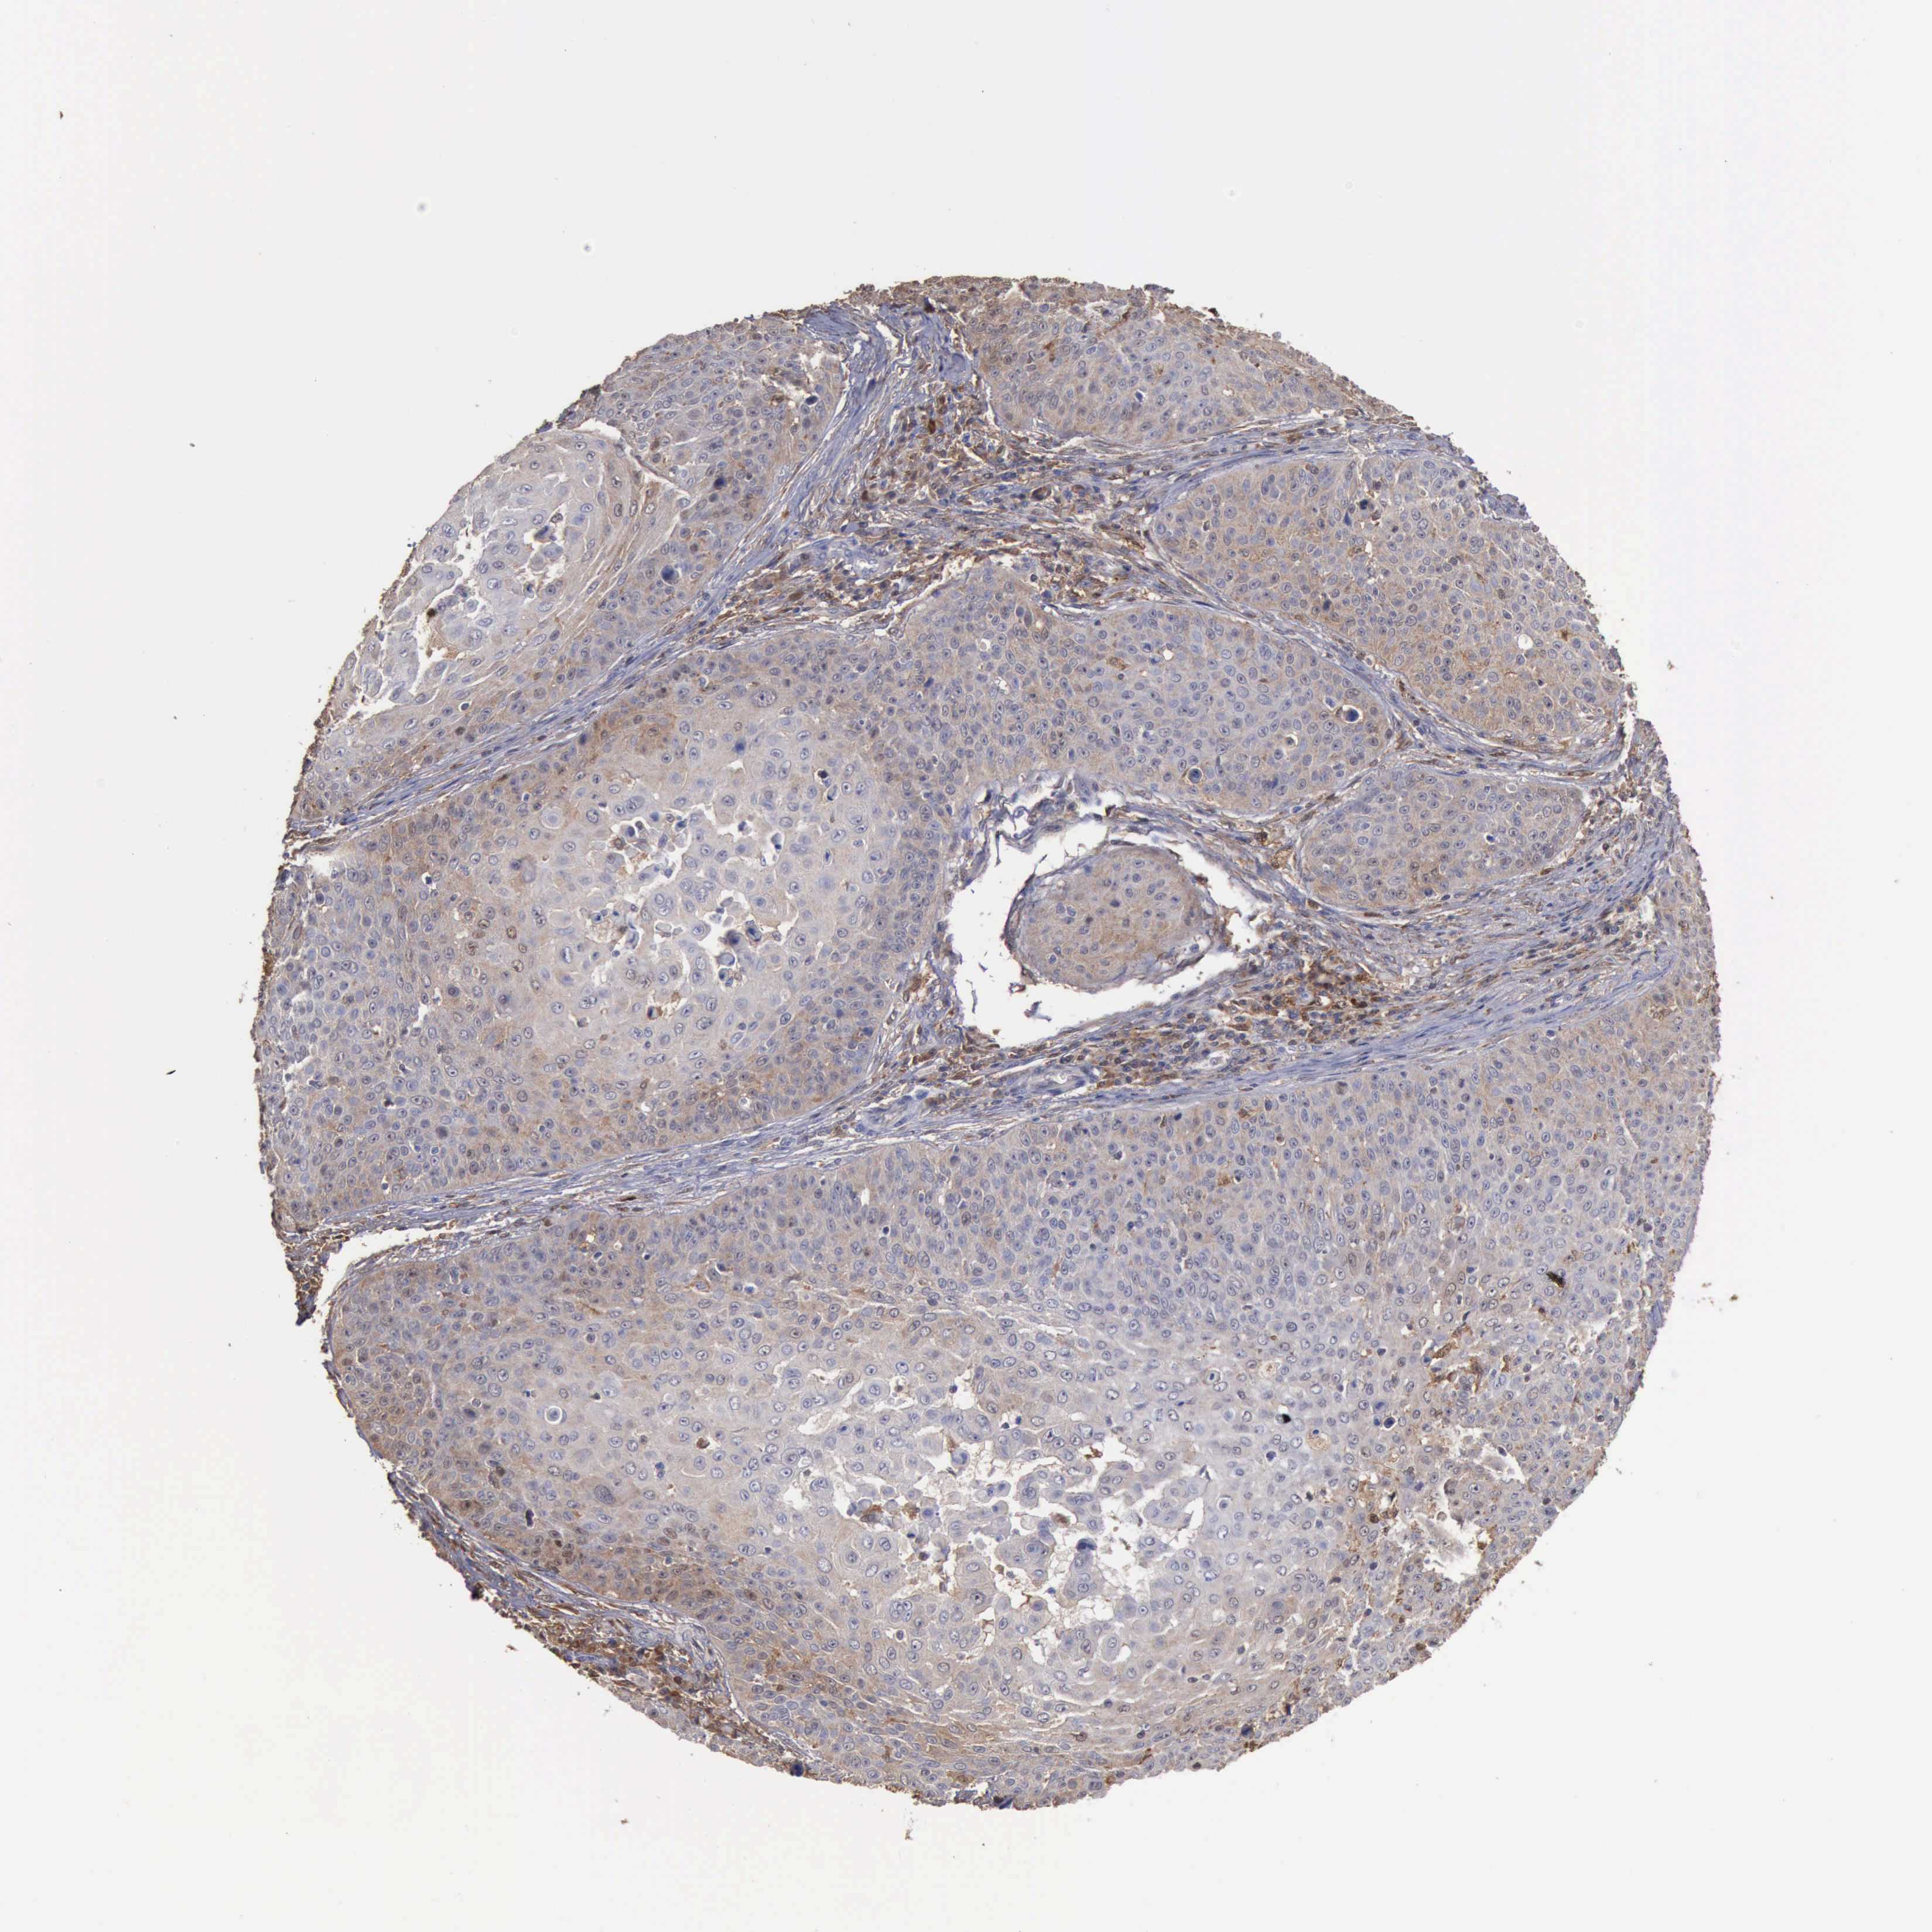

SKIN CANCER - Protein expressioni

A mouse-over function shows sample information and annotation data. Click on an image to view it in a full screen mode. Samples can be filtered based on level of antibody staining by selecting one or several of the following categories: high, medium, low and not detected. The assay and annotation is described here.

Each image is clickable and will lead to virtual microscopy that enables deeper exploration of all samples and also displays staining intensity scores, fraction scores and subcellular localization as well as patient and tissue information for each sample.

Antibody HPA000931

Staining

High

Medium

Low

Not detected

Intensity

Strong

Moderate

Weak

Negative

Quantity

>75%

75%-25%

<25%

None

Location

Nuclear

Cytoplasmic/membranous

Cytoplasmic/membranous,nuclear

Squamous cell carcinoma, NOS

Basal cell carcinoma